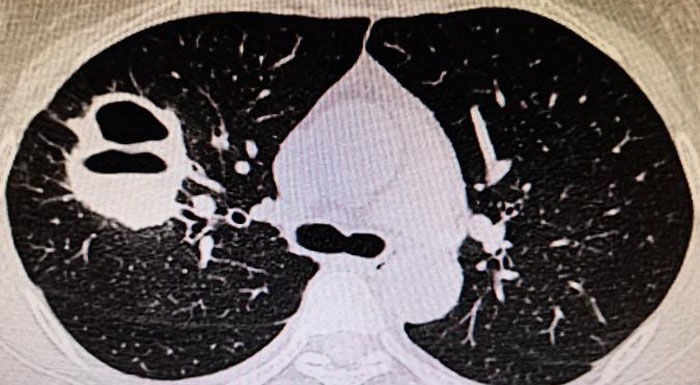

9、当肺CT出现如下情况,这可能是ANCA相关性血管肺部表现。